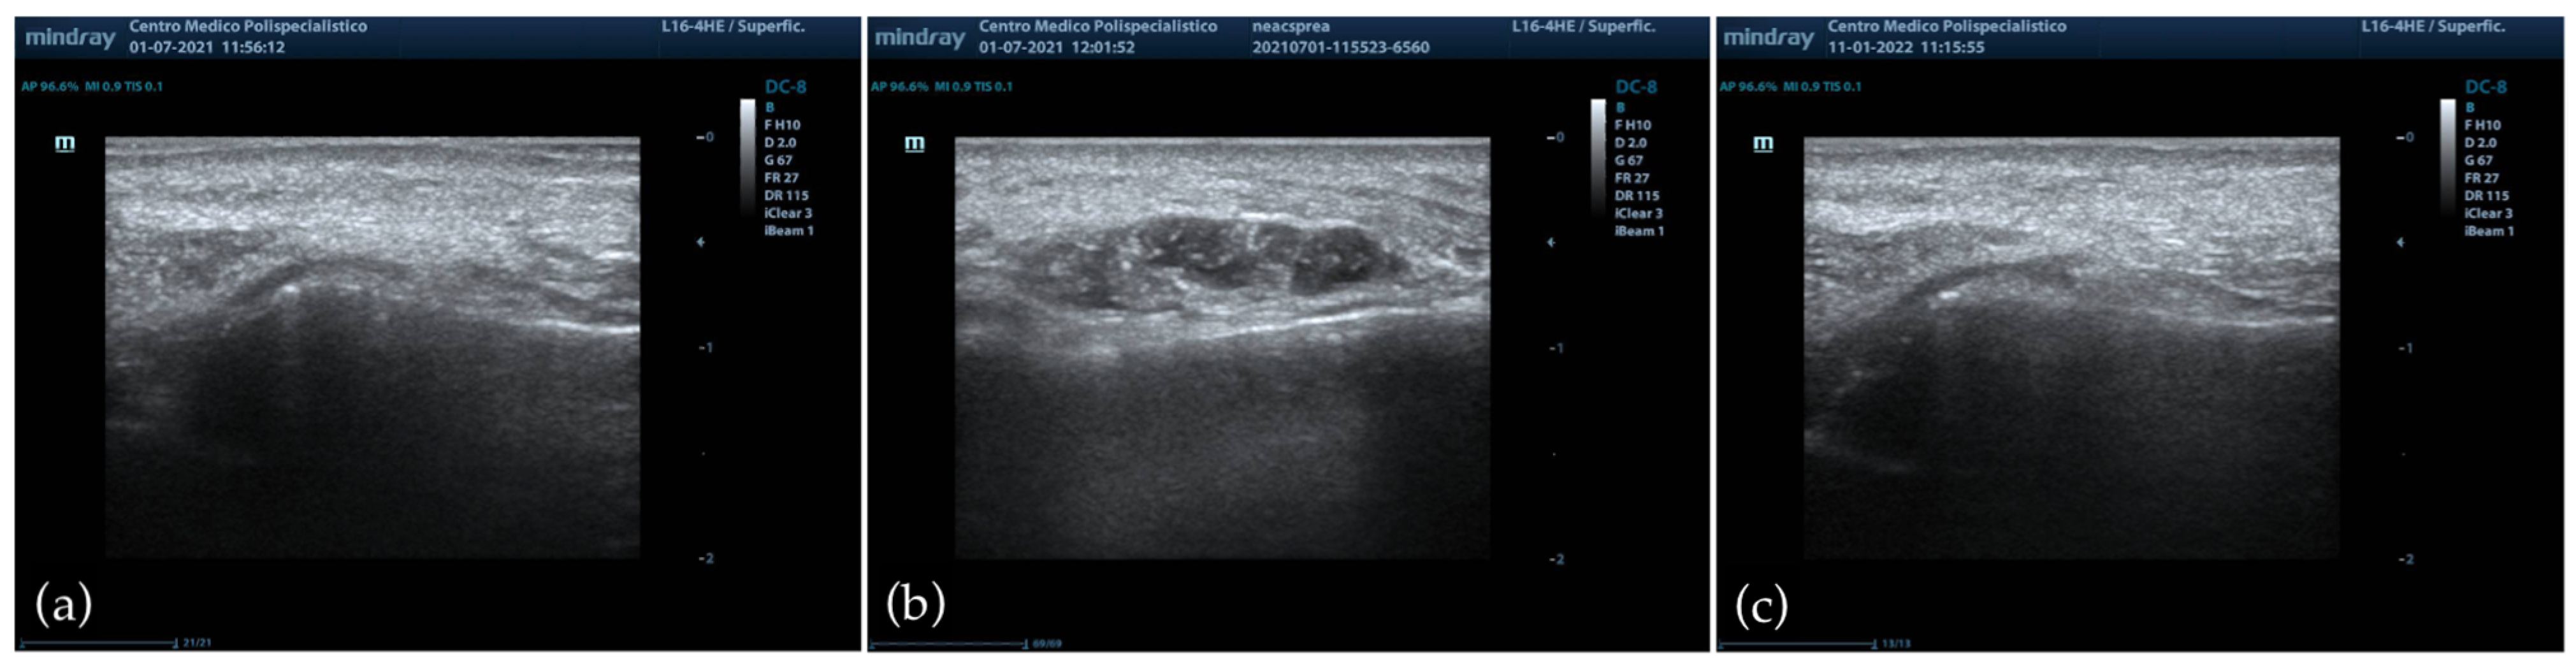

3.4. Ultrasound Evaluation